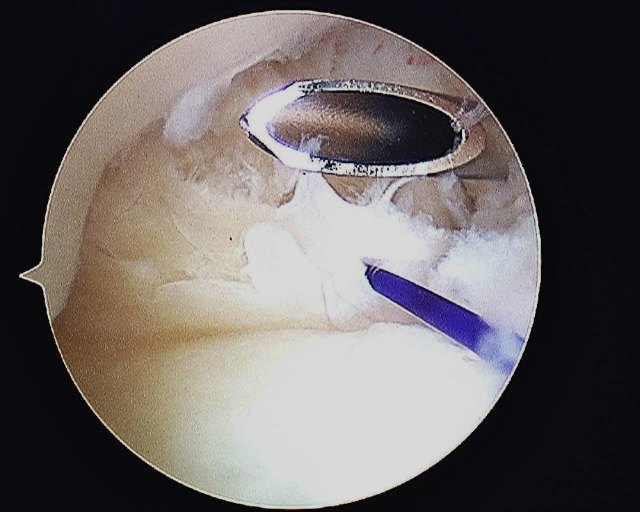

The cannula is passed into the joint again to pass a suture shuttle. I use the PDS 3/0 as a suture shuttle.

The 1st PDS suture that was passed through the TFCC is shuttled back into the joint and out of the capsule.